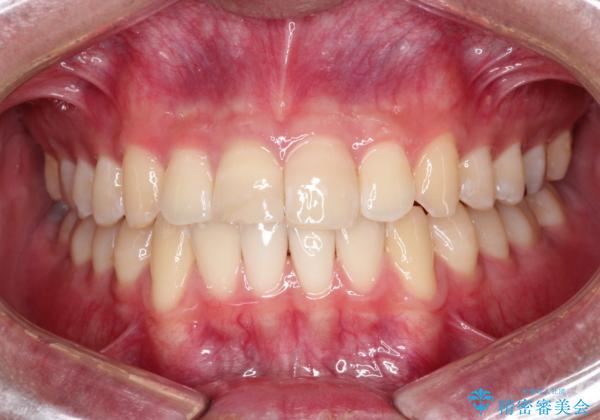

【ホワイトニング】右上前歯の歯茎の辺りが暗いのが気になる。

- 右上1番の色が暗いのを主訴に来院されました。

治療手順としましては、マイクロスコープ(歯科用顕微鏡)を使用し、元々入っていた詰め物のCR(プラスチック)を除去します。その後、歯の中に薬剤を入れ、蓋をします。2週間後に来院して頂き、白くなっているかを確認します。ご本人がご満足頂く白さになるまで、これを3~4回繰り返します。今回は1回で患者様がご満足されたので治療を終了しています。